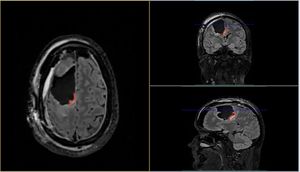

Meet my tumor

Time to cut to the chase. This is my brain tumor. There are many like it, but this one is mine. I've nicknamed him Gary Glia. Gary because it is a seemingly unpopular name nowadays in the UK (can't imagine why...), so it seemed quite appropriate. And Glia because it is the type of cell in my brain that has gone tumorous.

Gary is an unpaying tenant that has taken up residence in my head. What a prick!

A few days later I had a meeting with the neurosurgeon where I was shown the above images. Now full respect to the neurosurgeon I spoke too, I like him. He was straight down the line and straight to the point. No sugar coating, no forewarning about the size of the tumor. After 30 minutes of chatting about all of the above, he simply pulled his phone out and showed me image number 1 you see above. You could say I wasn't exactly prepared for the image, a understatement if ever there was one. But in all honesty I don't think I ever would be. So it was a good tactic. Make it quick and painless, just like ripping off a band-aid!

- He's big... look at the size of this unit. I'm amazed I can even function at all to be honest!

- He's of the type called oligodendroglioma and currently believed to be a Grade 2 (slow growing) tumor. Wondering how you pronounce that? Isn't YouTube great!

- He's very rare, with only 1,217 people diagnosed with this type in the US every year out of a population of 328 million!

- He's a number of years old. The neurosurgeon said a couple of years, but I personally suspect he could be 7 or 8 years old due to other symptoms in my past I now think could be related.